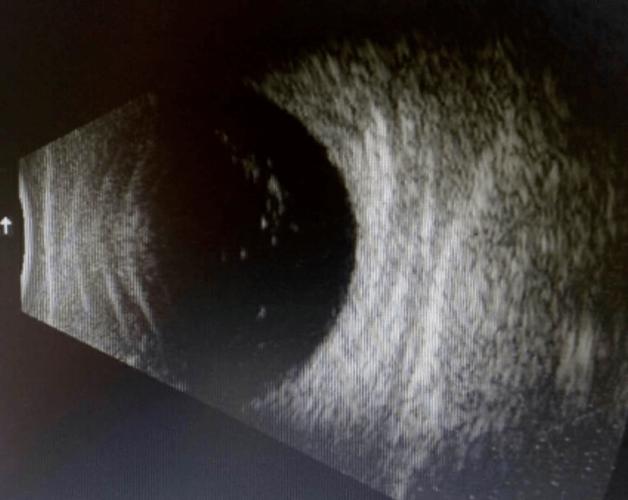

当玻璃体混浊时,玻璃体内可见絮状,条状回声,后运动明显,网膜在位.

玻璃体混浊b超图片

玻璃体混浊b超图

玻璃体混浊b超